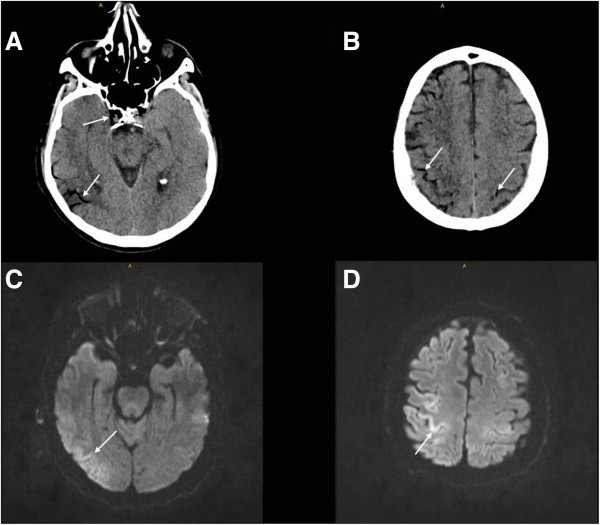

After a few seconds tachycardia ceased spontaneously but neurologic examination revealed a comatose patient with ping-pong gaze, decerebrate rigidity and positive Babinski response bilaterally. Mechanical ventilation was initiated with 100% oxygen since vascular air embolism was suspected. Furthermore, the patient was placed in partial left lateral decubitus position in order to entrap possible air in the right ventricle. Head CT showed massive air entrapment in cortical branches of both middle cerebral arteries, predominantly on the right side, and in the cavernous sinus (Figure 1). Since the patient was in need of critical care medicine we were not able to administer hyperbaric therapy. Thus, in order to reduce brain injury we decided to apply moderate hypothermia with a target bladder temperature of 33°C for 24 hours. Hypothermia was immediately induced with rapid free floating ice cold saline infusions (4°C, 25 ml/kg body weight) and after the diagnostic procedures by an external cooling system. Transthoracic echocardiography detected no intraventricular air. One hour and fifteen minutes after the first imaging, CT angiography showed normal cerebral blood vessels and complete resolution of the intracranial air. During rewarming the patient developed generalized myoclonus which did not respond to intravenous valproic acid, phenytoin and levetiracetam. Only propofol resulted in a discontinuation of myoclonus. The following days the patient increasingly regained consciousness and could be extubated on day ten. At that time MRI of the brain demonstrated multiple bihemispheric and cortially localized areas of restricted diffusion along the gyri (Figure 1). Sixteen days after the event the patient was discharged to a rehabilitation facility with a multimodal neglect and a moderate hemiparesis of the left extremities. Three months later his Rankin scale score remained 4.

Figure 1.

CT and MRI in cerebral air embolism. The initial head CT shows air entrapment in cortical branches of both middle cerebral arteries and in the cavernous sinus (arrows in A and B). On day ten MRI of the brain demonstrates cortically localized areas of restricted diffusion along the gyri (arrows in C and D).

Our report emphasizes that unenhanced CT of the head is capable to detect CAE if performed directly after symptom onset. Immediate brain imaging is thus required to verify the diagnosis. However, the absence of intracerebral air on CT does not exclude the diagnosis (Muth and Shank 2000). MRI demonstrated cortical ischemia predominately in the territory of the right middle cerebral artery. The gyriform pattern of restricted diffusion has been observed in several cases of CAE previously (Caulfield et al. 2006; Verro 2010; Koster et al. 2012) and may be the result of end-arterial occlusion and endothelial damage by air bubbles (Sobolewski et al. 2012). Interestingly, these cortical DWI changes resemble laminar necrosis on MRI in patients with hypoxic brain injury. If this finding exhibits a diagnostic value of CAE in cases without detection of intracerebral air on CT remains unclear and should be evaluated in prospective studies.